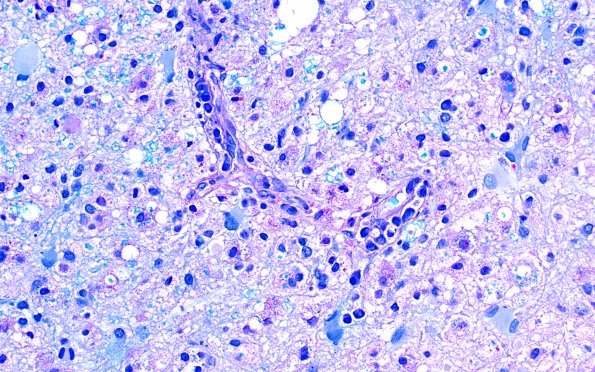

Washington University Experience | MYELIN (IMMUNE-MEDIATED) | Inflammatory Demyelination | 16C4 Inflammatory Demyelination (Case 16) LFB-PAS 40X 1

Luxol fast blue-PAS stain shows significant loss of myelin and phagocytosed myelin debris in macrophages.